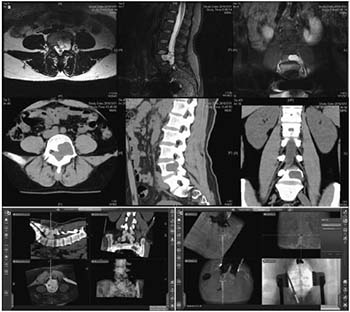

20171023161255 Figure 2 Preoperative, intraoperative, and postoperative images of patients in the thoracic intraspinal meningioma resection and pedicle screw fixation group. (a) Cervical thoracic vertebrae computed tomography shows a high-density tumor shadow in the thoracic spinal canal (T1-T4). Magnetic resonance imaging shows T2 image isointensity in the spinal canal (T1-T4). An enhanced scan shows a significantly enhanced area located in the ventral spinal cord that has invaded the intervertebral foramen. (b) Intraoperative microscopy shows a spinal cord ventral tumor, originating in the dura mater. (c) Intraoperative microscopy shows nearly total resection of the spinal cord ventral tumor, with the spinal cord remaining intact. (d, e) Intraoperative T2 pedicle screw implantation is performed under real-time navigation. The entry direction, angle, and depth of the screw is according to the navigation plan. (f, g, h) After screw implantation, an O-arm two-dimensional lateral scan shows good screw positioning. The O-arm three-dimensional scan found that the T1 bilateral pedicle screws are well positioned and do not penetrate the bone cortex. The T4 left pedicle screw position is also good. The left pedicle screw is in the lateral vertebrae, and no lung injury is seen between the vertebral body and rib. The screw position was not adjusted intraoperatively because it is within the acceptable range.

20171023161341 Figure 3 Preoperative, intraoperative, and postoperative images of the lumbar spinal canal of a patient in the internal and external schwannoma resection and pedicle screw fixation group. (a) Lumbar computed tomography (CT) shows an L4-5 intraspinal isodense tumor and a damaged L4 left pedicle and vertebral body. Magnetic resonance imaging (MRI) shows an iso- and hyperintensive signal tumor at L4-5 on the intraspinal T2 image. It is located on the left side of the spinal canal and has invaded a vertebral body and the intervertebral foramen. (b) Fusion of the CT and MRI images, in combination with an intraoperative O-arm and navigation technique, identifies the tumor site and border. (c) Intraoperative L5 pedicle screw implantation is performed under navigation. The screw’s direction, angle, and depth can be seen to match the navigation plan. (d) After screw implantation, an intraoperative O-arm two-dimensional lateral scan shows that the screw position is good. (e) An O-arm three-dimensional (3D) scan shows that the L3 pedicle screw position is good, and does not penetrate the bone cortex. (f) An O-arm 3D scan shows that the L5 left pedicle screw position moves away from the vertebral body and penetrates the rough pedicle bone cortex; (g) An O-arm scan was conducted again to introduce the navigation system as part of the correction of the L5 left pedicle screw, getting it to a good position. (h) An O-arm 3D scan shows that the L4 right pedicle screw position is good. It does not penetrate the bone cortex. Screws are difficult to implant in the left pedicle and vertebral body due to tumor invasion. (i) A lateral lumbar radiography scan, 7 days postoperatively, shows firm screw fixation and good positioning.

20171023161407 Figure 4 Preoperative, intraoperative, and postoperative images of patients in the nearly total sacrococcygeal chordoma resection and pedicle screw fixation group. (a) Lumbosacral vertebral computed tomography shows an S1-3 intraspinal isodense tumor and a severely damaged vertebral body. An enhanced magnetic resonance imaging scan shows S1-3 intraspinal internal and external tumors and a vertebral body that has been invaded and damaged. (b) Intraoperative L4 left pedicle screw implantation is performed under navigation. The direction, angle, and depth of the screw entery can be seen to match the navigation plan. (c) Intraoperative right iliac screw implantation is conducted under navigation. The direction, angle, and depth of the screw entering can be seen according to the navigation plan. (d) After screw implantation, an O-arm two-dimensional lateral scan shows good screw positioning. (e) A lateral lumbar radiographic scan, 7 days postoperatively, shows firm pedicle and iliac screw fixation and good positioning.